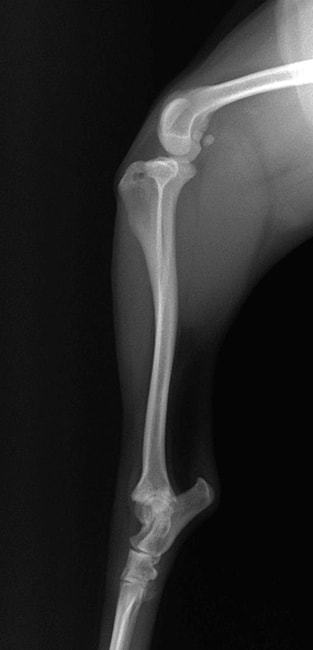

■ 症例22 ポメラニアン 1歳5か月 去勢雄

左後肢の挙上を主訴に来院した。整形学的検査、レントゲン検査より左右の膝蓋骨脱臼(左GradeⅡ〜Ⅲ、右Grade Ⅱ)を認めた。また、脛骨の前方引き出し試験の際に、引き出し兆候は認められないものの、疼痛が認められたため、前十字靭帯の損傷が疑われた。術中における、目視および関節内の操作によって、前十字靭帯の損傷や過伸展といった異常が認められなかったため、膝蓋骨脱臼の整復のみ実施した。手術手技は縫工筋及び内側広筋の解放、脛骨粗面の外側転位、滑車ブロック形造溝術、内外側関節包の縫縮を実施した。本症例は跛行もなく経過良好である。しかし、頸骨高平部の角度(TPA)が 右26.2°、左24.9°であり、解剖学的に前十字靭帯損傷のリスクが高いことから今後の経過に注意が必要である。